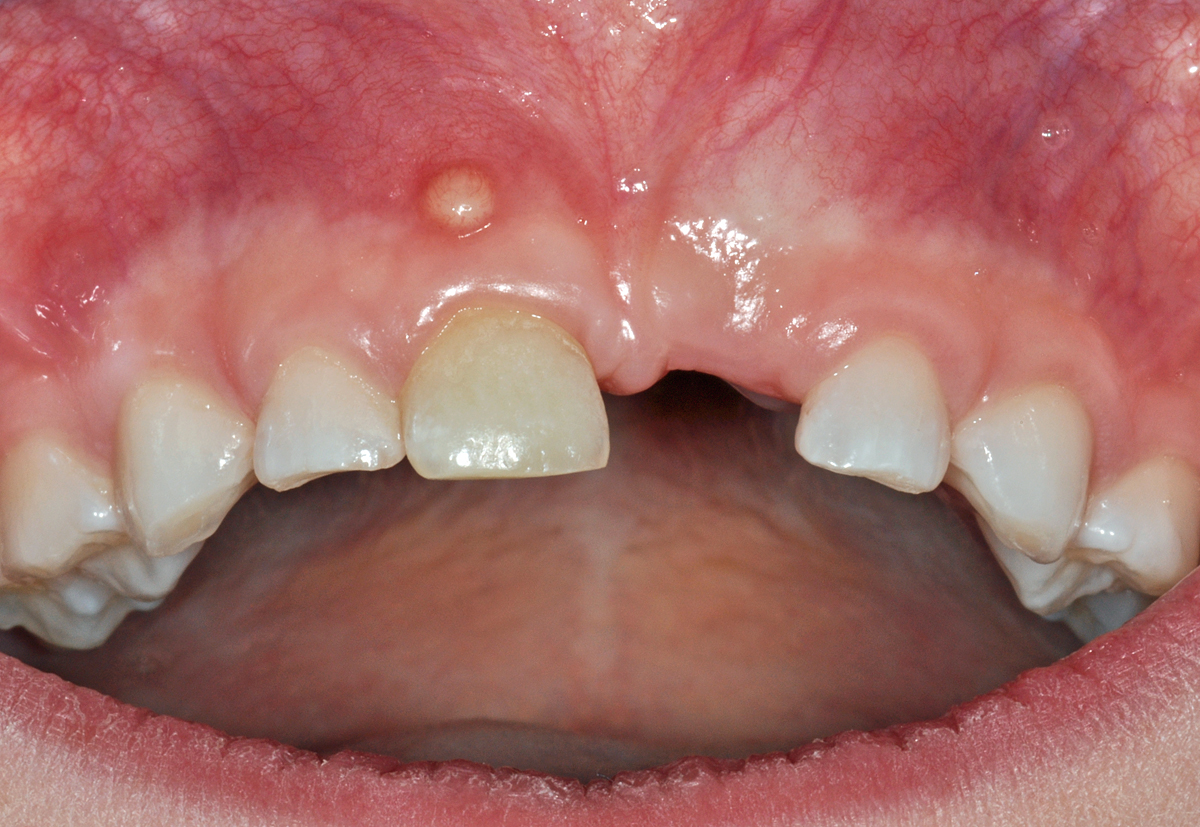

Dieser Fall zeigt einen knapp 7 Jahre alten Patienten, der sich schon vor einiger Zeit bei einem Sturz mit dem Fahrrad den mittleren Milch-Schneidezahn oben links (61) herausgeschlagen hat.

Offensichtlich ist dabei auch der rechte obere mittlere Milch-Schneidezahn (51) in Mitleidenschaft gezogen worden, denn er wurde anlässlich einer Kontrolle ein Jahr zuvor schon als verfärbt notiert (das ist auch auf den Bildern zu erkennen). Bei der neuerlichen Kontrolle zeigte sich an der Mundschleimhaut oberhalb des Zahnes 51 eine kleine, rundliche Erhebung (Pfeil).

Dabei handelt es sich nach klinischer Beurteilung um einen kleinen Abszess (eine eitrige Entzündung), ausgehend vom Zahn 51. In vielen Fällen ist eine solche Entzündung bei Kindern chronisch und verläuft ohne oder mit nur sanftem Schmerz. Oft entleert sich der Eiter dieser Entzündung spontan; man spricht dann von einer Fistel.